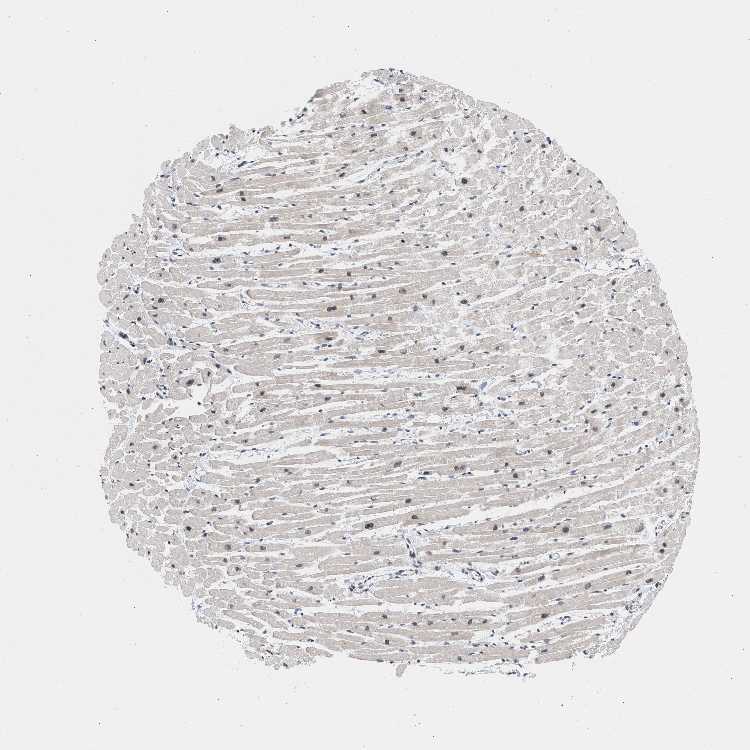

TISSUE PRIMARY DATA HEART MUSCLE Show tissue menu

HEART MUSCLE - Antibody stainingi

Antibody staining in the annotated cell types in the current human tissue is reported as not detected, low, medium, or high, based on conventional immunohistochemistry profiling in selected tissues. This score is based on the combination of the staining intensity and fraction of stained cells.

Each image is clickable and will lead to virtual microscopy that enables deeper exploration of all samples and also displays staining intensity scores, fraction scores and subcellular localization as well as patient and tissue information for each sample.

Antibody HPA018401Antibody HPA018410Antibody HPA018441

Cardiomyocytes LowLowMedium